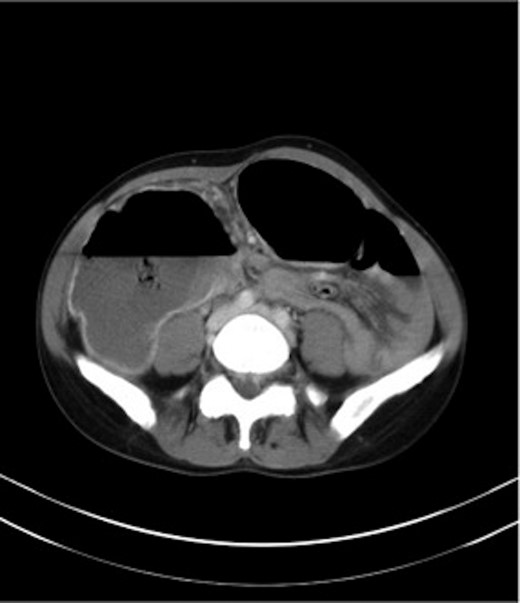

A gastrografin enema (Fig. 4) failed to demonstrate any flow beyond the mid-transverse colon. A presumptive diagnosis of transverse colon obstruction was made and the patient was taken to theatre.

Gastrografin enema (Case 2) demonstrating no flow beyond the mid-transverse colon.

Laparotomy revealed an adhesive band extending from the gastrocolic omentum to the right fallopian tube causing a closed-loop obstruction of right half of transverse colon, ascending colon and terminal 5 cm of ileum. The band was divided. The bowel was viable. Appendicectomy was performed and most of the gas in the colon was aspirated via the appendicular stump prior to its ligation.